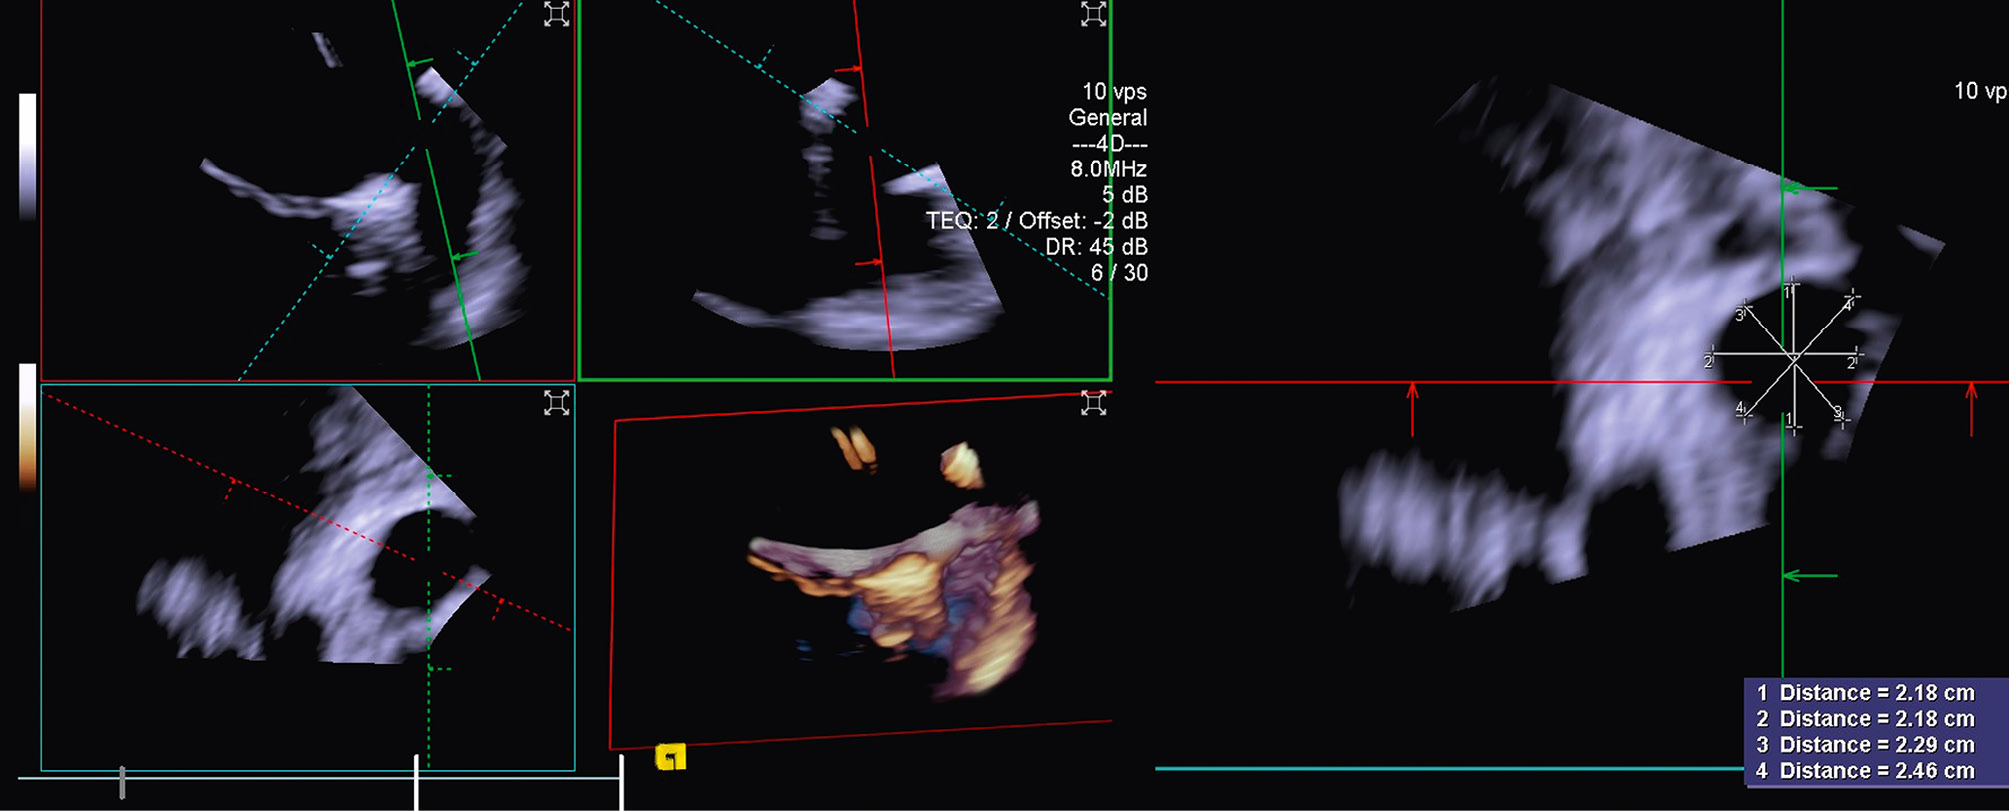

Imaging the MV with ICE implies crossing the interatrial septum and positioning the imaging catheter in the left atrium, a step that can be technically challenging. The TSP is performed using simultaneous biplane imaging with the ICE catheter positioned in the middle of the right atrium and retroflexed towards the septum (Figure 7A). A preshaped stiff wire is carefully positioned into the upper left pulmonary vein under fluoroscopic and ICE guidance (Figure 7B). Predilatation of the septum is required to facilitate the advancement of the ICE catheter into the LA while tracking the trajectory of the wire (Figure 7B). This can be done either by advancing and retracting the TEER-guiding catheter or through preparatory balloon septostomy using a 12-14 mm over-the-wire percutaneous transluminal angioplasty balloon. Once the ICE catheter has been placed successfully into the left atrium, it is followed by the guiding sheath, and the implant itself is then advanced towards the diseased MV (Figure 7C). While the ICE catheter usually follows the curve of the delivery system, a position below it (Figure 7D) or the use of the right and left deflexion knob minimises shadowing artefacts and avoids direct interaction with the TEER device or any other catheter used for the intervention. The key advantage of RT 3D catheters is the ability to produce MPR that facilitates simultaneous optimisation of the trajectory and orientation in several planes and on the 3D view from the atrium (Figure 8, Figure 9A-Figure 9B-Figure 9C, Moving image 9-Moving image 10-Moving image 11). At the end of the procedure, closure of the interatrial septum should be considered (Figure 9D), since the defect is usually larger than after conventional TEER due to the manipulation of two catheters through the same access. Closure can be easily guided with the ICE catheter back to the right atrium (Figure 9E). Mini-TOE or a paediatric probe (without 3D capabilities), as well as transthoracic echocardiography26 are additional confirmatory imaging modalities that can be used in combination with ICE (Figure 9F).

Figure 7. ICE-guided transseptal puncture. A) Transseptal puncture using biplanar imaging with the ICE catheter retroflexed in the middle of the RA. Needle tenting is seen simultaneously in two dimensions. B) Position of the delivery catheter over the diseased mitral valve. C) After wire placement and septum predilatation, the ICE catheter is moved into the LA following the trajectory of the stiff wire. A paediatric TOE probe without 3D capacity is inserted into the oesophagus. D) Position of the ICE catheter below the TEER system to avoid shadowing artefacts. 3D: three-dimensional; ICE: intracardiac echocardiography; LA: left atrium; RA: right atrium; TEER: transcatheter edge-to-edge repair

Figure 8. Three-dimensional true surgical view and left ventricular view of the mitral valve after TEER. A) 3D true surgical view; (B) left ventricular view. 3D: three-dimensional; TEER: transcatheter edge-to-edge repair

Figure 9. ICE-guided mitral valve transcatheter edge-to-edge repair. A) Implantation of two clips and leaflet capture under ICE visualisation; (B) final result after implantation of two clips for correction of a posterior flail; (C) 3D ICE view of the MV after implantation of two clips; (D) large iatrogenic ASD visualised from the right atrium and crossed by a wire; (E) ASD closure using a 14 mm Amplatzer Septal Occluder under ICE guidance; (F) final result with mild residual MR as shown by transthoracic echocardiography at discharge. 3D: three-dimensional; ASD: atrial septal defect; ICE: intracardiac echocardiography; LA: left atrium; LV: left ventricle; MR: mitral regurgitation; MV: mitral valve; RA: right atrium; RV: right ventricle